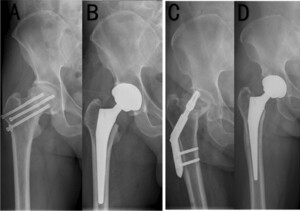

Dual Mobility (DM) Arthroplasty

Instability remains the most common complication of THA after FNF, and DM constructs have emerged as a strategy to mitigate this risk. The design incorporates a mobile polyethylene liner within a fixed metal shell, creating two articulating surfaces and increasing jump distance.

Registry data strongly support the stability advantage of DM. The Swedish Hip Arthroplasty Register, analysing >10,000 THAs performed for FNFs, found that dislocation rates were significantly lower with DM compared to conventional THA (1.3% vs 2.2% at two years when posterior approach was used).65 A multicentre French registry reported similar findings, with dislocation incidence reduced by 50–70% in elderly fracture populations when DM was employed.66

Randomised controlled trial data remain limited, but observational cohorts are consistent. In a large matched study, DM reduced dislocation rates without increasing revision for other causes.67 However, infection remains a leading cause of DM revision, with cumulative rates of 2–3% at five years, which is similar to conventional THA in this setting.63,66 Some series suggest higher heterotopic ossification with DM, though this has not been associated with poorer PROMs.68

Concerns about long-term polyethylene wear and intraprosthetic dislocation persist. However, modern highly crosslinked polyethylene has significantly reduced this risk, with 10-year survival of DM constructs exceeding 95% in fracture cohorts.69 The additional cost of DM implants has been offset in several economic models by reductions in revision and reoperation rates secondary to dislocation.70

Overall, DM THA is increasingly considered the implant of choice for displaced FNFs in active elderly patients at high risk of dislocation, particularly those requiring posterior approach exposure.65–67